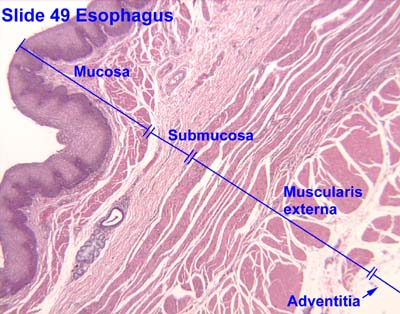

La mucosa bucal, al igual que toda mucosa, está conformada por 2 capas de

tejidos, de estructura y origen embriológico diferente:3

· Tejido epitelial, capa superficial de origen ectodérmico.

· Tejido conectivo (lámina propia o corion), capa subyacente de origen

ectomesenquimático (derivado de células de la cresta neural).

Entre ambos tejidos se encuentra la membrana basal, que se observa

ondulada por la presencia de papilas del corion y crestas epiteliales, que

facilitan la nutrición entre el epitelio avascular y el conectivo vascular.

Puede existir una tercera capa de tejido conectivo laxo, la submucosa,

presente en algunas zonas de la mucosa oral.

SUBMUCOSA:

Está capa está compuesta por tejido conectivo más denso destinado a unir la

mucosa a los tejidos subyacentes.

La submucosa puede estar presente o no como capa definida. Está presente

en zonas que requieren movimiento y que no están expuestas directamente al

choque masticatorio y está ausente en zonas donde el corion está firmemente

adherida a la estructura ósea subyacente.

Se constituye por tejido conectivo de espesor y densidad variables y en ella se

pueden encontrar vasos, nervios, tejido adiposo y glándulas salivales.